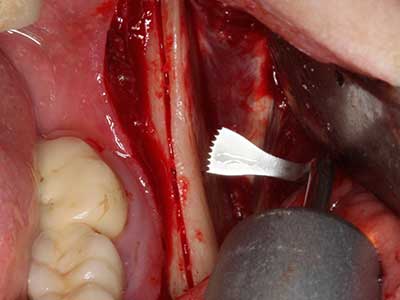

Indication: Apical resection

When surgical procedures are performed on bone in the immediate vicinity of sensitive structures such as blood vessels or nerves, rotary instruments pose a significant risk of iatrogenic injury. Piezoelectric devices can be helpful for preparation of bone covers and removal of hard tissue close to nerves, particularly for exposure of nerves after iatrogenic injury but also during nerve lateralization for resective and reconstructive procedures or implant placement (Fig. 17-20). Light contact between the piezotip and the nerve does not generally result in damage but proceeding incautiously with saw-like motions or attachments where a residual bone substrate remains may cause temporary or even permanent nerve damage. However, the risk of damage is considered to be substantially lower than when using saws or milling instruments (Pereira, Gealh et al. 2014).